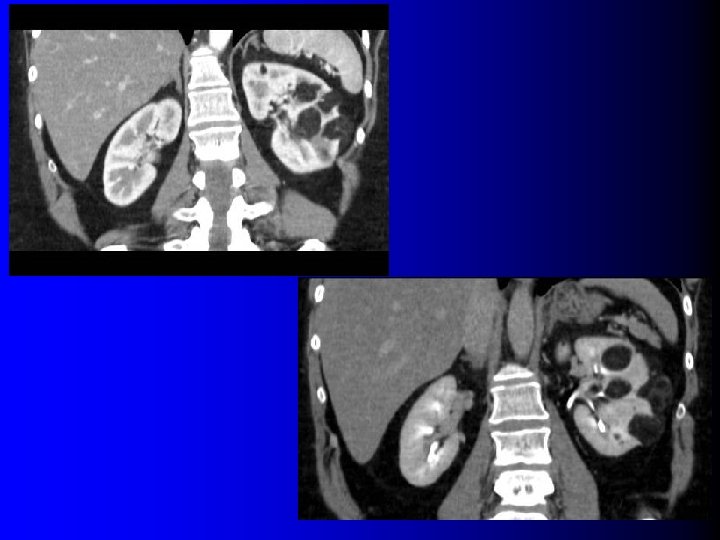

Tomodensitométrie Tumeur hypervasculaire avec plages de densité graisseuse (-10 UH à -100 UH) l l Intérêt : – Diagnostique – Thérapeutique : l Taille exacte l Localisation l Importance du contingent vasculaire l Technique d'examen rigoureuse: – Minimiser les effets de volume partiel l Coupes fines (millimétriques) l Examen sans injection

Tomodensitométrie Tumeur hypervasculaire avec plages de densité graisseuse (-10 UH à -100 UH) l l Intérêt : – Diagnostique – Thérapeutique : l Taille exacte l Localisation l Importance du contingent vasculaire l Technique d'examen rigoureuse: – Minimiser les effets de volume partiel l Coupes fines (millimétriques) l Examen sans injection

Intérêt de l'IRM? l Présence de graisse: – Hypersignal T 1 disparaissant après saturation de graisse – Déplacement chimique : India Ink artifact l Peu pratiquée en première intention – Grossesse – TDM non conclusive ?

Intérêt de l'IRM? l Présence de graisse: – Hypersignal T 1 disparaissant après saturation de graisse – Déplacement chimique : India Ink artifact l Peu pratiquée en première intention – Grossesse – TDM non conclusive ?

Saturation de graisse

Saturation de graisse